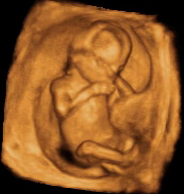

Desarrollo del feto de 15 semanas: se mueve, pero no lo notas

En la semana 15 de embarazo el tamaño del bebé es comparable a una naranja. En la ecografía, los movimientos del feto son muy evidentes: la criatura mueve ya con facilidad las articulaciones de los codos y las muñecas, abre y cierra los puños de sus manitas.

En cualquier ecografía de la semana 15 se observa la gran vitalidad de los bebés que tienen esta edad gestacional: sus estructuras básicas están ya formadas y aún campan a sus anchas dentro del útero materno.